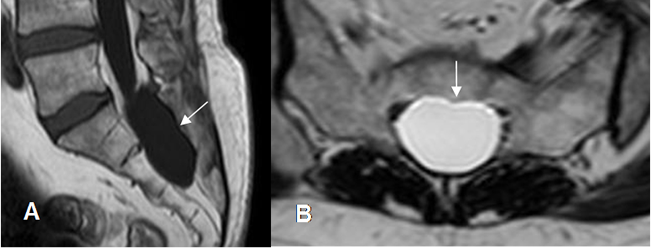

Fig 227. Quiste radicular.

A: RM sagital en T1 y B: RM axial en T2. Lesión ovalada y de consistencia líquida, que ocupa el canal medular a nivel del sacro.